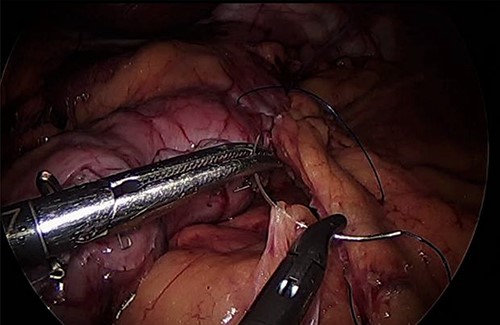

As for the LRA, ports are inserted in similar fashion as the LLA but with more to the right side. An additional port at the right midclavicular line is an optional (Fig. 5). In Patient 1, we started with the LLA to control the blood pressure caused by the adrenal gland and to prevent unnecessary bleeding from occurring. Conversely, we started with LSG in Patient 2 because the priority was controlling his comorbidities by weight reduction. The right hepatic lobe was retracted to expose the subhepatic area. The right hepatic ligaments were released, exposing the inferior vena cava. Dissection lateral to the IVC was continued exposing the right adrenal (Fig. 6). Complete dissection of the adrenal gland was completed and the pedicle was controlled using energy device (Fig. 7). There was constant communication with the anesthesia team during the surgery. After complete dissection of the adrenal gland, it was placed in the endobag and the LSG was conducted similar to the above-mentioned steps (Fig. 8).